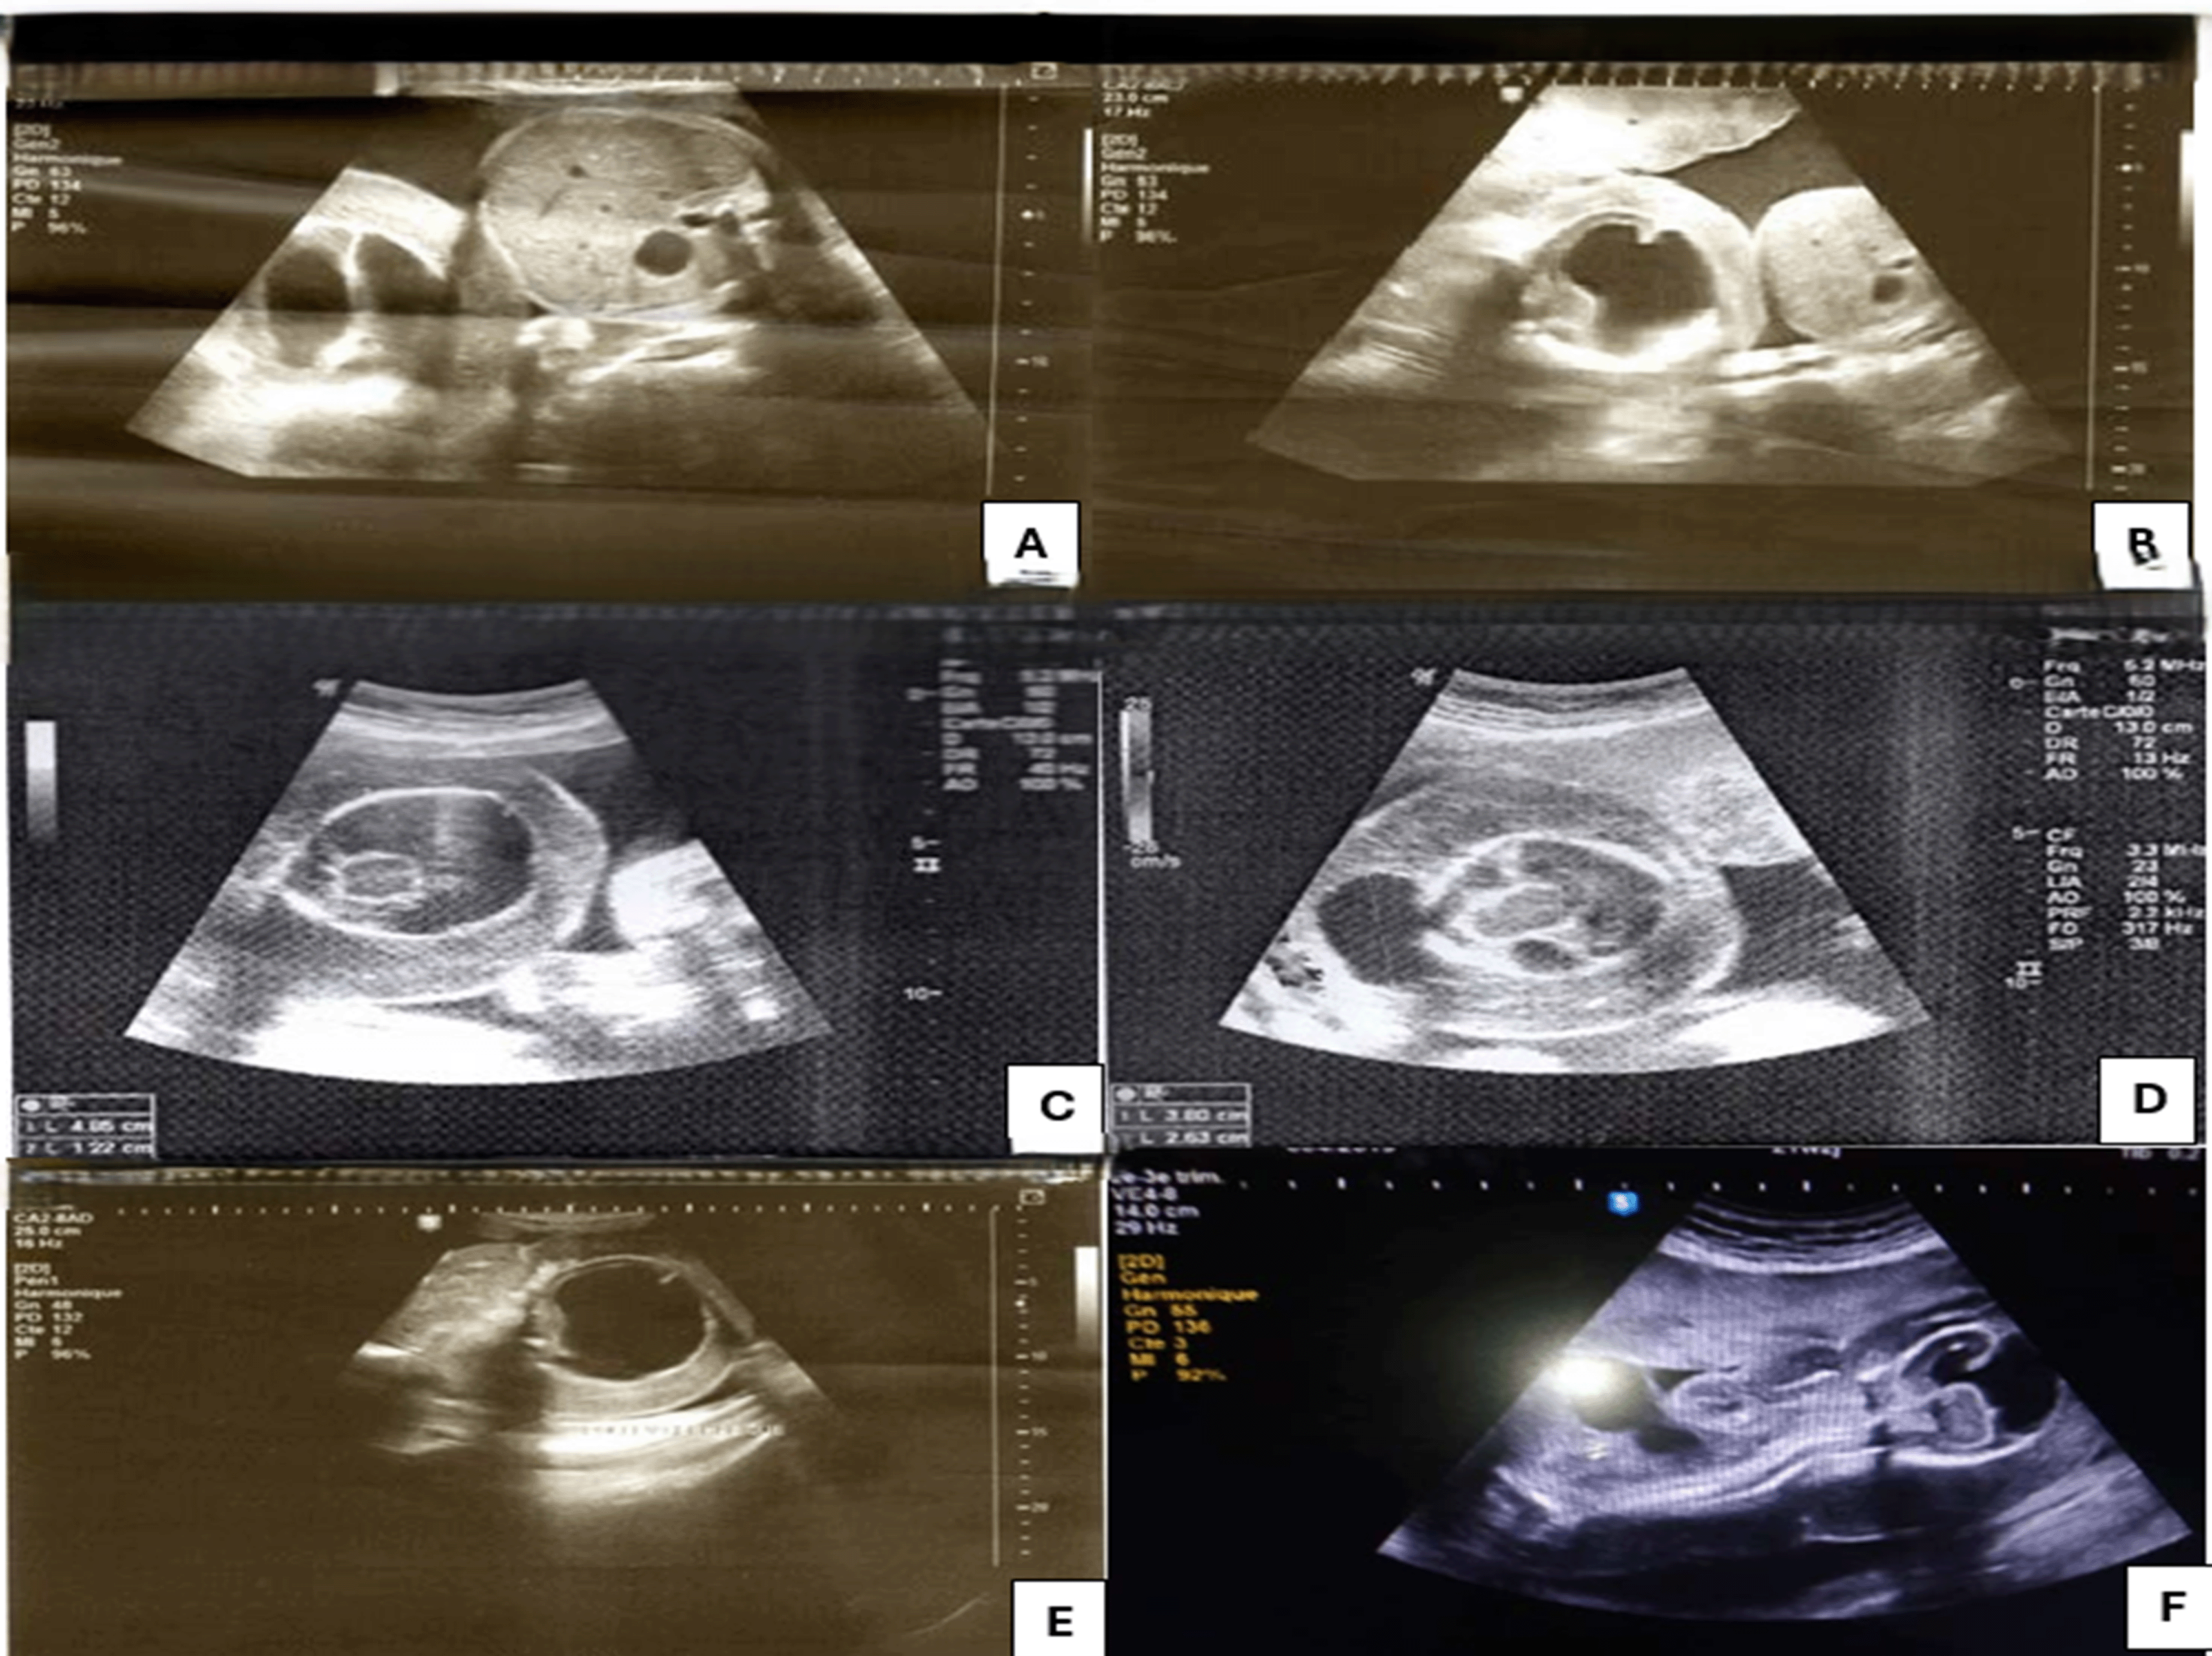

A weekly ultrasound check was carried out, showing: a favorable evolution of the healthy twin; on the other hand, for the acardiac twin, an increase in volume with obvious polyhydramnios was observed.

The evolution was marked by the appearance of uterine distension (uterine height = 50 cm) with uterine contractions (the cervical length = 2.6 cm) Hence tocolytic treatment was initiated as well as fetal lung maturation at 30 weeks.

At 34 weeks + 4 days, the patient presented with significant respiratory difficulty; hence, a cesarean section was decided in collaboration with the neonatologists and gave birth to two babies:

- The first was female, weight = 2150 g, size = 44 cm, cranial perimeter = 31 cm. Her Apgar scores at the first and fifth minutes were 9 and 10, respectively.

- The second twin was a female acardiac fetus weighting = 3700 and with a height of 30 cm. The fetus has two lower limbs, but no upper limbs ( Figure 3).